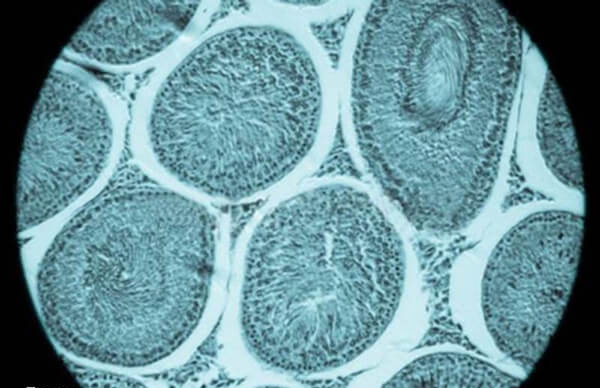

多囊这类患者卵巢内小卵泡数量多,若不控制,取卵后易发生卵巢过度刺激综合征,拮抗剂方案可帮助控制促排卵过程,获得适量卵子。

3、窦卵泡数目较多者

一般年龄小于35岁,卵巢功能正常,但窦卵泡数量为7-14个,既往没有卵巢高反应或低反应情况的人群,拮抗剂方案对这类人群促排卵效果较好,取卵数、妊娠率较高。